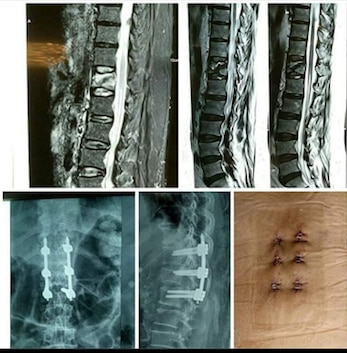

Dr Rahul Rane is an Orthopaedic Surgeon with 16 years of experience in the field of Orthopaedics. He has taken his Master's Degree in Orthopaedic from Mumbai's reputed Lokmanya Tilak Medical College. He has vast experience in treating all kinds of Orthopaedic and Spine problems He is a master in Spine surgery with cutting-edge Endoscopic spine Surgery techniques with no complications. Patients can walk on the same day after endoscopic spine-surgery. He had done Advance Spine Surgery fellowship Training in Korea. He performs all kinds of joint replacement surgeries with excellent results. His operated knee and Hip replacement patients walk full weight bearing after 1 day. His patient's post Surgery walking freely and performing all kinds of work. He is a fitness freak, an avid Marathon runner. He is passionate about making his patients recover faster. “My patient should resume to routine earliest” is his motto.